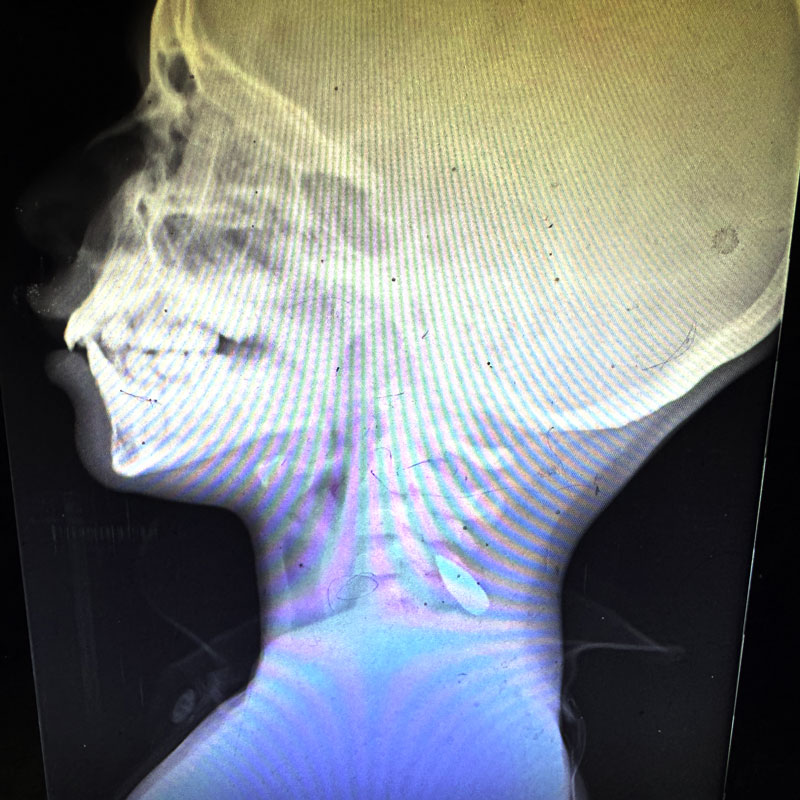

Deca povređena u Gazi Foto: AA/ABACA / Abaca Press / Profimedia Deca povređena u Gazi Foto: AA/ABACA / Abaca Press / Profimedia Deca povređena u Gazi Foto: AA/ABACA / Abaca Press / Profimedia "Svakog dana su nam donosili decu sa ranama od metka u glavi": Stravična svedočenja lekara iz Gaze o teškim zločinima izraelske vojske autor: Ivana Kešanski Svet 10. okt. 2024. 20:34 2 Podeli vest: Lekari koji u ratom razorenoj Gazi leče ljude ispričali su sa kakvim su se sve stvarima susretali. Mnogi od njih su svedočili o teško ranjenim i ubijenim civilima, a najpotresnije su priče o deci koju su im donosili sa ranama od metka na glavi. Podeli vest: Oglas Doktor Feroz Sidva je volontirao u bolnici u Kan Junisu dve nedelje, a za to kratko vreme je svedočio stravičnim prizorima. On je u saradnji sa Njujork tajmsom intervjuisao svoje kolege iz različitih bolnica u Gazi. “Radio sam kao hirurg u Gazi od 25. marta do 8. aprila. Volontirao sam u Ukrajini i Haitiju, a odrastao sam u Flintu, Mičigen. Video sam nasilje i radio u ratnim zonama. Ali od mnogih stvari koje su se isticale tokom rada u bolnici u Gazi, jedna me je posebno pogodila: Gotovo svakog dana dok sam bio tamo, video sam novo malo dete koje je pogođeno u glavu ili grudi, a gotovo svi su kasnije preminuli. Ukupno trinaest. U to vreme, pretpostavio sam da je ovo delo posebno sadističkog vojnika u blizini. Ali nakon što sam se vratio kući, upoznao sam lekara urgentne koji je radio u drugoj bolnici u Gazi dva meseca pre mene. ‘Nisam mogao da verujem koliko sam dece video pogođenih u glavu’, rekao sam mu. Na moje iznenađenje, odgovorio je: ‘Da, i ja isto. Svakog dana’”, ispričao je Sidva. Fotografije rendgenskih snimaka pogođene dece je objavila dr Mimi Sajed, koja je radila u Kan Junisu od 8. avgusta do 5. septembra. Rana od metka u lobanji deteta Foto: Dr. Mimi Syed | Rana od metka u lobanji deteta Foto: Dr. Mimi Syed Rekla je: „Imala sam više pacijenata pedijatrijske dobi, uglavnom mlađe od 12 godina, koji su bili pogođeni u glavu ili levu stranu grudi. Obično su to bili pojedinačni hici. Pacijenti su dolazili mrtvi ili u kritičnom stanju i ubrzo nakon dolaska umirali.“ Ogromna količina informacija o razmerama razaranja u Gazi prikupljena je putem satelitskih podataka, humanitarnih organizacija i Ministarstva zdravlja Gaze. Međutim, Izrael ne dozvoljava novinarima ili istražiteljima ljudskih prava ulazak u Gazu, osim malog broja novinarskih putovanja sa izraelskom vojskom, a priče palestinskih novinara iz Gaze nisu dovoljno čitane, uprkos neverovatnim rizicima koje preuzimaju da bi izveštavali odatle. Ali postoji grupa nezavisnih posmatrača koji su ovaj rat videli sa terena, iz dana u dan: volonterski zdravstveni radnici. “Kroz lične kontakte u medicinskoj zajednici i mnogo pretraživanja na internetu, uspeo sam da stupim u kontakt sa američkim zdravstvenim radnicima koji su radili u Gazi od 7. oktobra 2023. godine. Mnogi imaju porodične ili verske veze sa Bliskim istokom. Drugi, poput mene, nemaju, ali su osetili potrebu da volontiraju u Gazi iz različitih razloga. Koristeći pitanja zasnovana na sopstvenim zapažanjima i razgovorima sa kolegama doktorima i medicinskim sestrama, sarađivao sam sa Tajms Opinion kako bih ispitao 65 zdravstvenih radnika o onome što su videli u Gazi. Pedeset sedam, uključujući mene, bilo je voljno da podeli svoja iskustva. Ostalih osam učestvovalo je anonimno, ili zbog toga što imaju porodicu u Gazi ili na Zapadnoj obali, ili zbog straha od odmazde na radnom mestu”, ispričao je Sidva. Rana od metka u lobanji deteta Foto: Dr. Mimi Syed | Rana od metka u lobanji deteta Foto: Dr. Mimi Syed "U roku od četiri sata sam video šest dece sa ranom od metka u lobanji" Kako je rekao 44 intervjuisana lekara i medicinskih tehničara je videlo više slučajeva male dece upucane u glavu ili u grudi u Gazi. “Jedne večeri na odeljenju za urgentnu medicinu u roku od četiri sata sam video šestoro dece uzrasta od pet do 12 godina sa ranom od metka u lobanji”, ispričao je dr Mohamad Rasoul Abu-Nuvar. „Pedijatrijski pacijenti sa prostrelnim ranama lečeni su na podu, često su krvarili na podu bolnice zbog nedostatka prostora, opreme, osoblja i podrške. Mnogi su nepotrebno umrli“, rekla je medicinska sestra Nina Ng. Dr Mark Perlmuter je rekao da je video nekoliko dece upucane sa ranama od metka velike brzine, i u glavu i u grudi. „Naš tim je brinuo o četvoro-petoro dece, uzrasta od 5 do 8 godina, koja su sva pogođena pojedinačnim hicima u glavu. Svi su se u isto vreme javili u Hitnu pomoć. Svi su umrli“, rekao je dr Irfan Galarija. Bolničarka Ranija Avaneh je videla dete pogođeno u vilicu. „Bio je potpuno budan i svestan šta se dešava. Zurio je u mene dok se gušio svojom krvlju dok sam pokušavala da je isišem slomljenim aparatom za usisavanje”, rekla je ona. Doktor Kavaja Ikram je video trogodišnjaka i petogodišnjaka sa po jednom rupom od metka na glavi. “Na pitanje šta se dogodilo, njihov otac i brat su rekli da im je rečeno da se Izrael povlači iz Kan Junisa. Pa su se vratili da vide da li je nešto ostalo od njihove kuće. Tamo je, rekli su, čekao snajperista koji je upucao oba deteta”. Među žrtvama su bila i deca mlađa od dve godine. Doktorka Alija Katan je videla 18-mesečnu devojčicu sa prostrelnom ranom na glavi. „Videla sam mnogo dece. Po mom iskustvu, prostrelna rana je često bila u glavi. Mnogi su imali neizlečivo, trajno oštećenje mozga. Bila je skoro svakodnevna pojava da deca pristižu u bolnicu sa prostrelnim ranama u glavi“, rekao je dr Ndal Fara. Oni su videli i slučajeve gde su deca umirala od gladi, bolesti i povreda koje bi inače bile izlečive. “Ono što su američki lekari i medicinske sestre videli iz prve ruke u Gazi trebalo bi da oblikuje politiku Sjedinjenih Država prema Gazi. Smrtonosna kombinacija onoga što Human Rights Watch opisuje kao neselektivno vojno nasilje, onoga što Oxfam naziva namernim ograničavanjem hrane i humanitarne pomoći, gotovo univerzalnog raseljavanja stanovništva i uništavanja zdravstvenog sistema ima katastrofalne posledice na koje su mnogi stručnjaci za Holokaust i genocid upozorili pre skoro godinu dana”, navodi doktor Sidva. Foto: AA/ABACA / Abaca Press / Profimedia | Foto: AA/ABACA / Abaca Press / Profimedia Amerika saučesnik u zločinima Kako je rekao, američki zakon i politika dugo su zabranjivali transfer oružja nacijama i vojnim jedinicama koje učestvuju u teškim kršenjima ljudskih prava, posebno — kako jasno naglašava ažuriranje američke politike o konvencionalnom transferu oružja iz 2023. godine — kada su ta kršenja usmerena na decu. “Teško je zamisliti ozbiljnija kršenja ovog standarda od redovnog pucanja u glave male dece, novorođenčadi i njihovih majki koje umiru od gladi zbog blokirane humanitarne pomoći i uništene infrastrukture za vodu, kao i uništenog zdravstvenog sistema”, rekao je. On je pozvao SAD da hitno reaguje i prestane da šalje vojnu pomoć Izraelu. “U proteklih 12 meseci, naša vlada je imala moć da zaustavi protok američke vojne pomoći Izraelu. Umesto toga, dolivali smo ulje na vatru pri svakoj prilici, isporučivši preko 50.000 tona vojne opreme, municije i naoružanja od početka rata, prema ažuriranim podacima Ministarstva odbrane Izraela iz kraja avgusta. To se svodi na prosečno više od 10 transportnih aviona i dva teretna broda oružja nedeljno. Sada, nakon više od godinu dana razaranja, procene palestinskih žrtava kreću se od desetina hiljada do stotina hiljada. Međunarodni komitet spasa opisuje Gazu kao ‘najopasnije mesto na svetu za humanitarne radnike, kao i za civile’. UNICEF ocenjuje Gazu kao ‘najopasnije mesto na svetu za decu’. Oxfam izveštava da u Al-Mavasi, oblasti koju je Izrael proglasio za humanitarnu bezbednu zonu u Gazi, postoji jedan toalet na svakih 4.130 ljudi. U napadu 7. oktobra i u ratu koji je usledio ubijeno je najmanje 1.470 Izraelaca. Polovina talaca koji su ostali u Gazi navodno su mrtvi. I dok američki zvaničnici optužuju Hamas da produžava rat i ometa pregovore, izraelski mediji konstantno izveštavaju da je premijer Benjamin Netanjahu sabotirao pregovore o prekidu vatre s Hamasom i Hezbolahom, dok je nepromišljeno eskalirao sukob umesto da postigne dogovor koji bi mogao ostvariti mnoge od Izraelskih ratnih ciljeva, uključujući oslobađanje izraelskih talaca”, rekao je Sidva. Džo Bajden Foto:EPA-EFE/CHRIS KLEPONIS | Džo Bajden Foto:EPA-EFE/CHRIS KLEPONIS Kako je rekao administracija Džoa Bajdena i Kamale Haris ne može reći da nije znala šta rade. “Osam sadašnjih američkih senatora, 88 članova Predstavničkog doma, 185 advokata (uključujući desetine iz administracije) i 12 državnih službenika (koji su dali ostavke u znak protesta zbog naše politike prema Gazi) rekli su administraciji da je nastavak naoružavanja Izraela nezakonit prema američkom zakonu...Zajedno, Izrael i Sjedinjene Države pretvaraju Gazu u pustu divljinu. Ali nikada nije prekasno da se promeni kurs: mogli bismo zaustaviti izraelsko korišćenje našeg oružja, municije, avionskog goriva, obaveštajnih i logističkih podrški tako što bismo ih obustavili, i mogli bismo zaustaviti dotok oružja svim stranama najavom međunarodnog embarga na oružje Izraelu i svim palestinskim i libanskim oružanim grupama. Sprovođenje američkih zakona koji zahtevaju obustavu vojne pomoći Izraelu bio bi potez sa širokom podrškom: humanitarne organizacije, desetine članova Kongresa, većina Amerikanaca i ogromna većina članica Ujedinjenih nacija se slažu. Ovaj užas mora prestati. Sjedinjene Države moraju prestati da naoružavaju Izrael. A nakon toga, mi Amerikanci moramo ozbiljno da preispitamo sebe”, zaključio je lekar u opširnom eseju za Njujork tajms. "Nema kraja paklu": Snimci iz Gaze razotkrili laži izraelske vojske FOTO VIDEO Svet 7 Netanjahu navodno rekao da je živa polovina od 97 talaca koje Hamas drži u Gazi Svet 0 Godina oružanih sukoba Izraela i Hamasa: Osvetnički rat koji je doneo nove patnje u Gazi i tome, nazire li mu se kraj Emisije 0 gaza rat u Izraelu Pratite nas na društvenim mrežama: Koje je tvoje mišljenje o ovoj temi? Učestvuj u diskusiji ili pročitaj komentare Budite prvi koji će ostaviti komentar Pošalji komentar Pročitaj komentare (2)